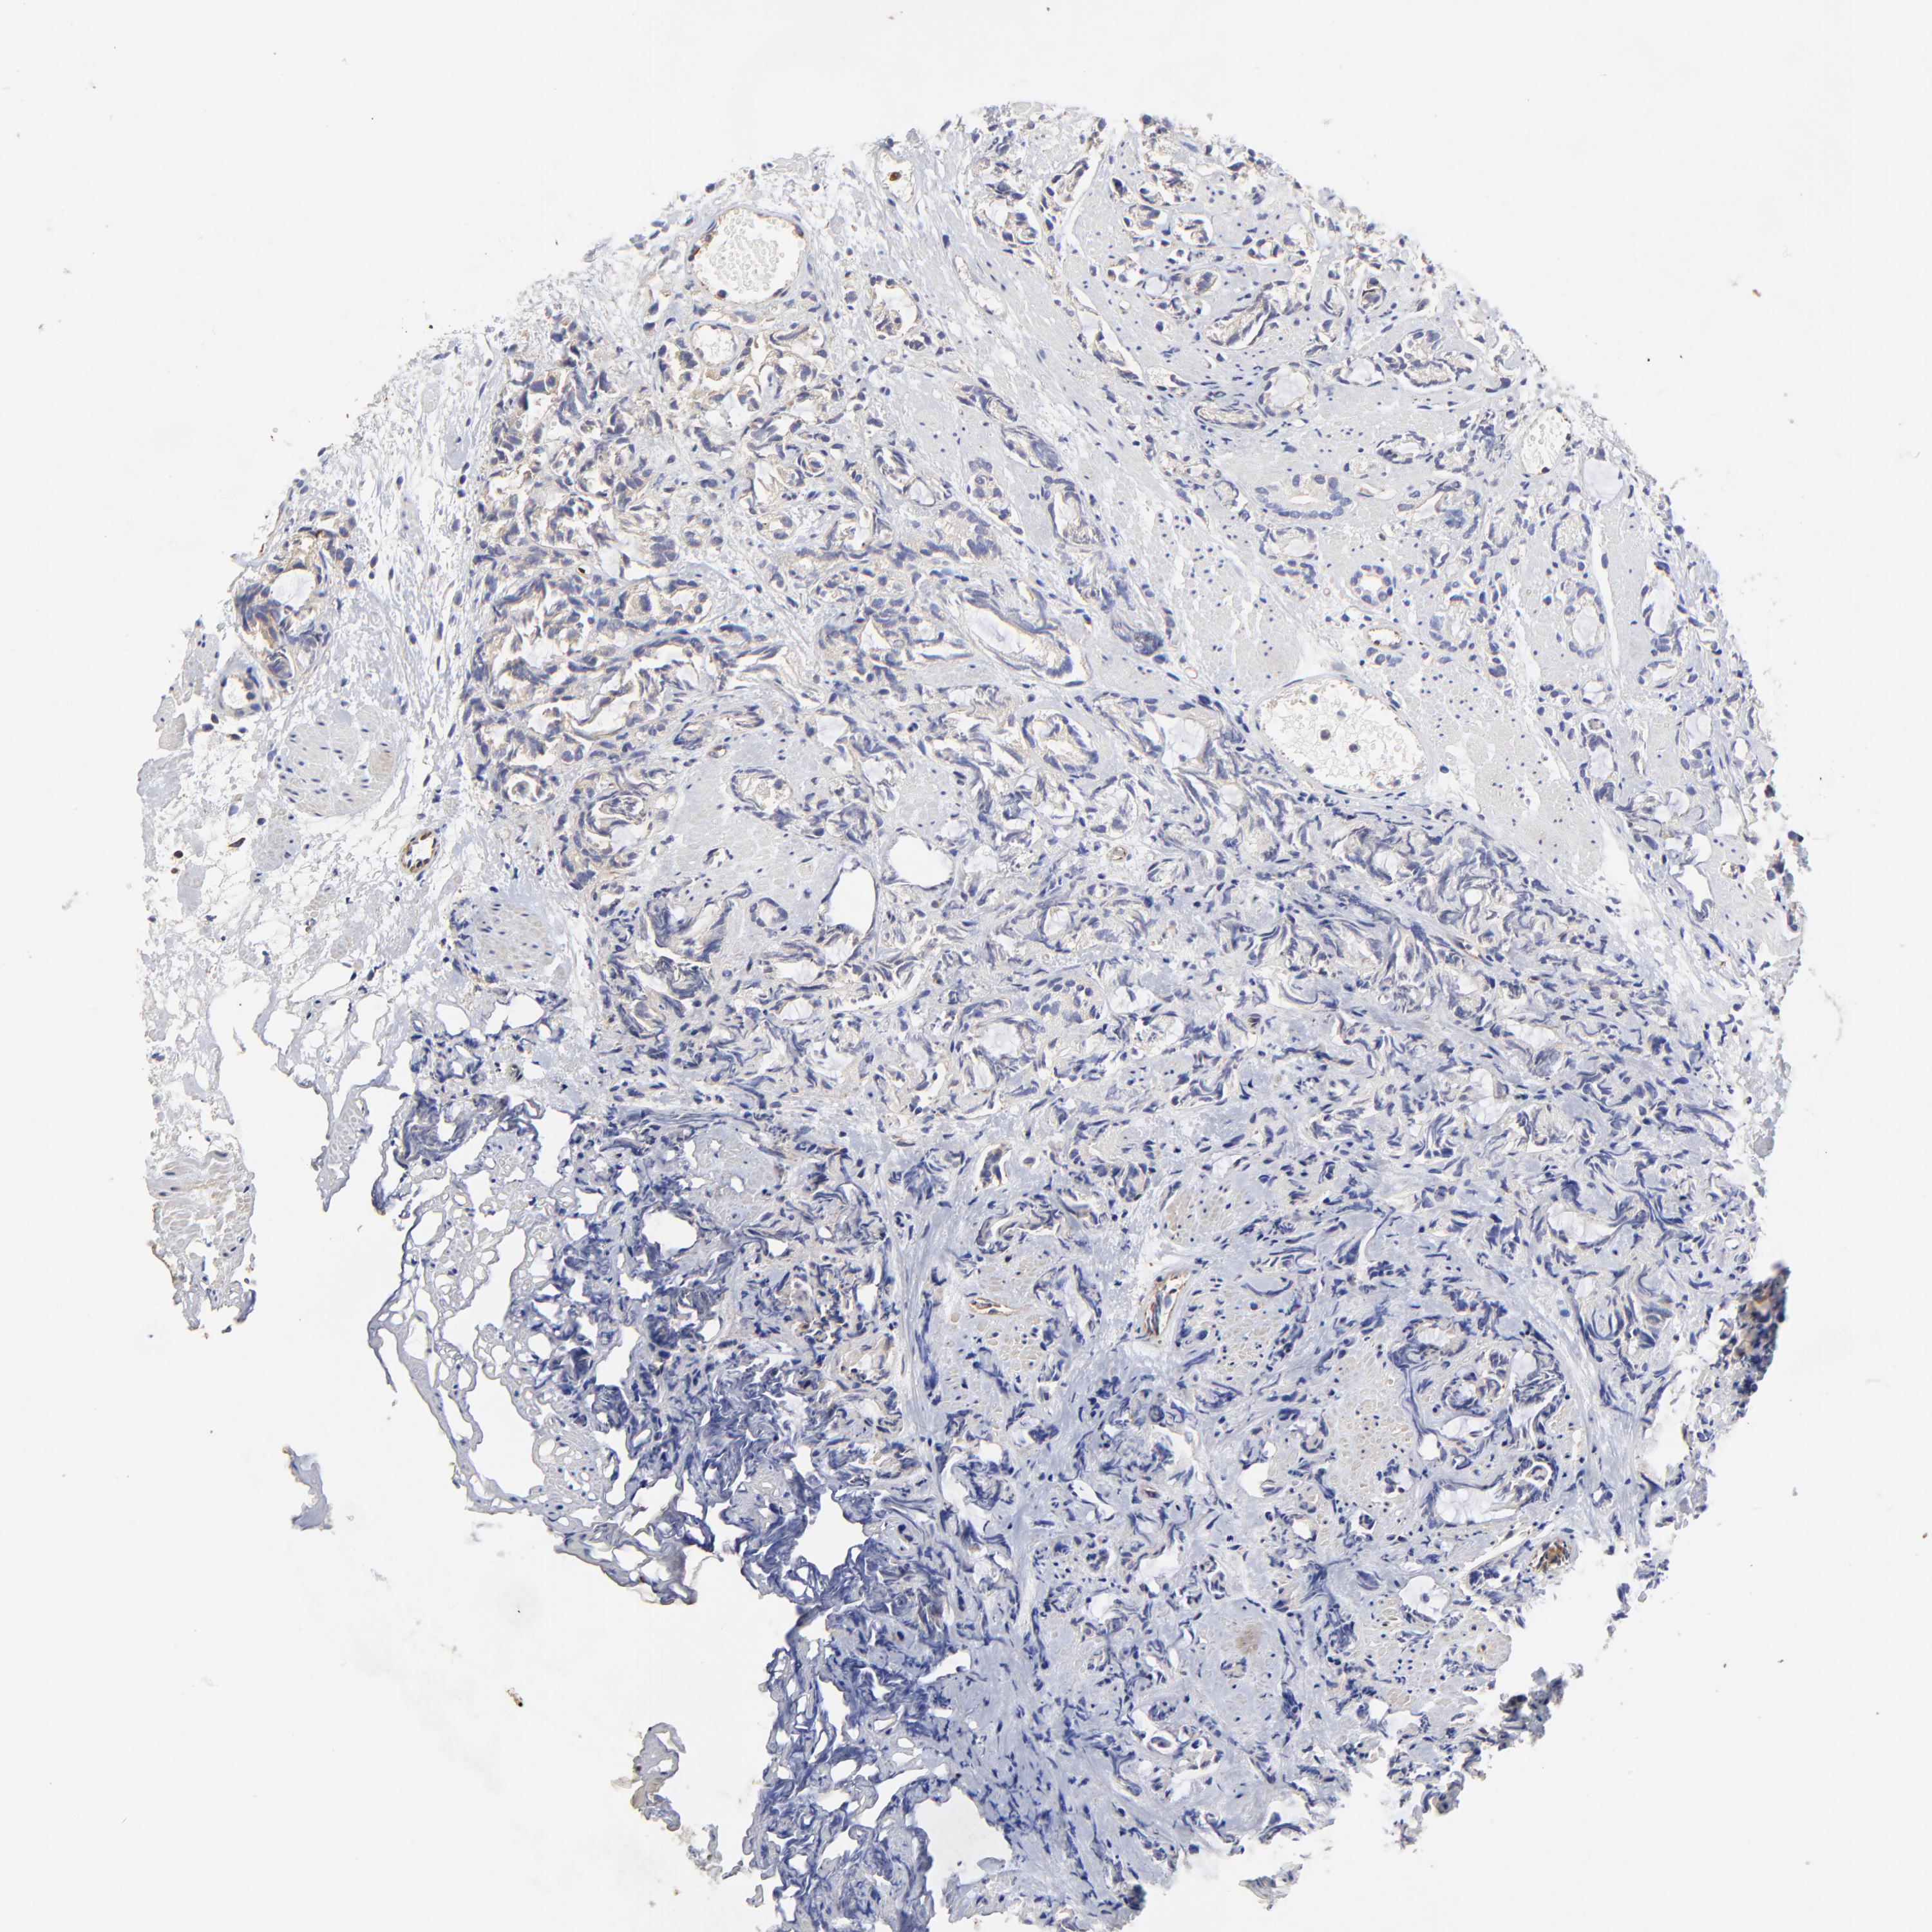

PROSTATE CANCER - Protein expressioni

A mouse-over function shows sample information and annotation data. Click on an image to view it in a full screen mode. Samples can be filtered based on level of antibody staining by selecting one or several of the following categories: high, medium, low and not detected. The assay and annotation is described here.

Note that samples used for immunohistochemistry by the Human Protein Atlas do not correspond to samples in the TCGA dataset.

Antibody stainingi

Antibody staining in the annotated cell types in the current human tissue is reported as not detected, low, medium, or high, based on conventional immunohistochemistry profiling in selected tissues. This score is based on the combination of the staining intensity and fraction of stained cells.

Each image is clickable and will lead to virtual microscopy that enables deeper exploration of all samples and also displays staining intensity scores, fraction scores and subcellular localization as well as patient and tissue information for each sample.

Antibody HPA002325

Staining

High

Medium

Low

Not detected

Intensity

Strong

Moderate

Weak

Negative

Quantity

>75%

75%-25%

<25%

None

Location

Nuclear

Cytoplasmic/membranous

Cytoplasmic/membranous,nuclear

Adenocarcinoma, Low grade

Adenocarcinoma, High grade